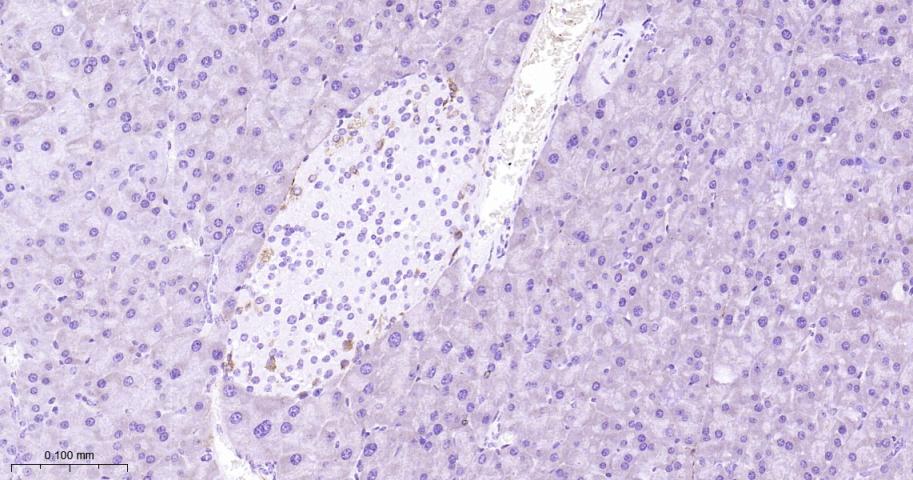

| 英文名称 | FAP Rabbit pAb |

| 中文名称 | 成纤维细胞激活蛋白α抗体 |

| 产品应用 | IHC-P=1:100-500, IHC-F=1:100-500, IF=1:100-500, ELISA=1:5000-10000 Not yet tested in other applications. |

| {IHC-P} | {1:100-500} |

文献和实验[IF={{ 7.145 }}] {Zhang, Bo, et al. "Enhanced anti-tumor activity of EGFP-EGF1-conjugated nanoparticles by a multi-targeting strategy." ACS Applied Materials & Interfaces (2016).} {IHC} {="Mouse"}

[IF={{ 4.8 }}] {Zhenfeng Liu. et al. Fibroblast Activation Protein–Targeted PET/CT with Al18F-NODA-FAPI-04 for In Vivo Imaging of Tendon Healing in Rat Achilles Tendon Injury Models. AM J SPORT MED. ;():} {IHC} {Rat}